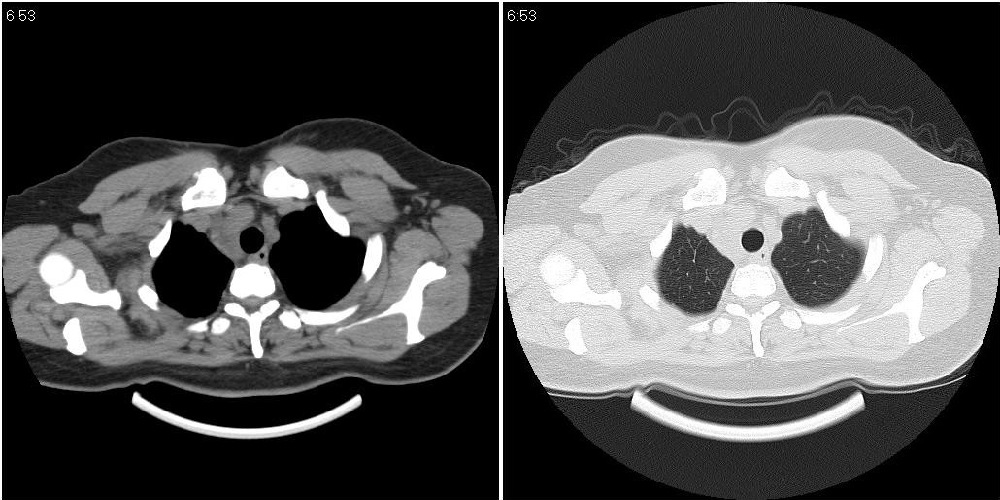

标题: CT24795:女性,47岁,右下腿静脉静脉曲张手术前体检,发现 [打印本页]

标题: CT24795:女性,47岁,右下腿静脉静脉曲张手术前体检,发现

囊性无明显占位效应:1淋巴管囊肿2畸胎瘤(其上部见小钙化)3前肠囊肿

右上纵隔囊性占位性病变;考虑淋巴管囊肿,不排除支气管囊肿。

支气管囊肿、囊性畸胎瘤、肠源性囊肿均有可能。

右上纵隔囊性占位性病变;考虑淋巴管囊肿,不排除支气管囊肿。 建议增强。

考虑淋巴管囊肿,不排除前肠囊肿。